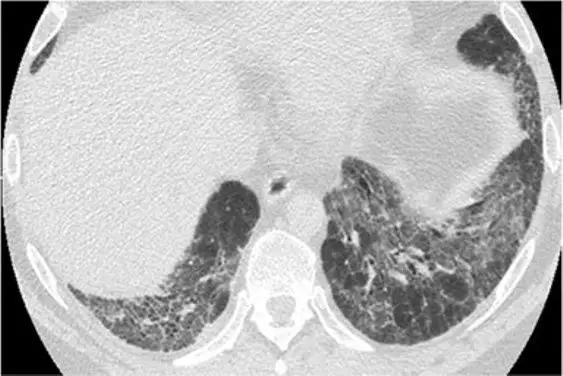

9、囊性病变伴磨玻璃影

特征是同时出现了两种HRCT模式。经典疾病:PJP。鉴别疾病:淋巴细胞性间质性肺炎、亚急性过敏性肺炎和脱屑性间质性肺炎。

10、马赛克征

这种模式的特征是增加和减低的密度混杂拼凑,这可能代表(1)分布不均的间质性疾病,(2)闭塞性小气道疾病和(3)闭塞性小血管疾病 。经典疾病:闭塞性细支气管炎(OB)。

鉴别疾病:慢性血栓栓塞性肺动脉高压可能由于斑片状的血管性低氧血症而表现出马赛克征。亚急性超敏性肺炎也可能表现出马赛克衰减模式,既表现为“间质性”病因,表现为衰减增加的区域(磨玻璃影不透明),又表现为“小气道疾病”病因,表现为衰减减少的区域,可能加剧。呼吸性细支气管炎也可能是这种模式。